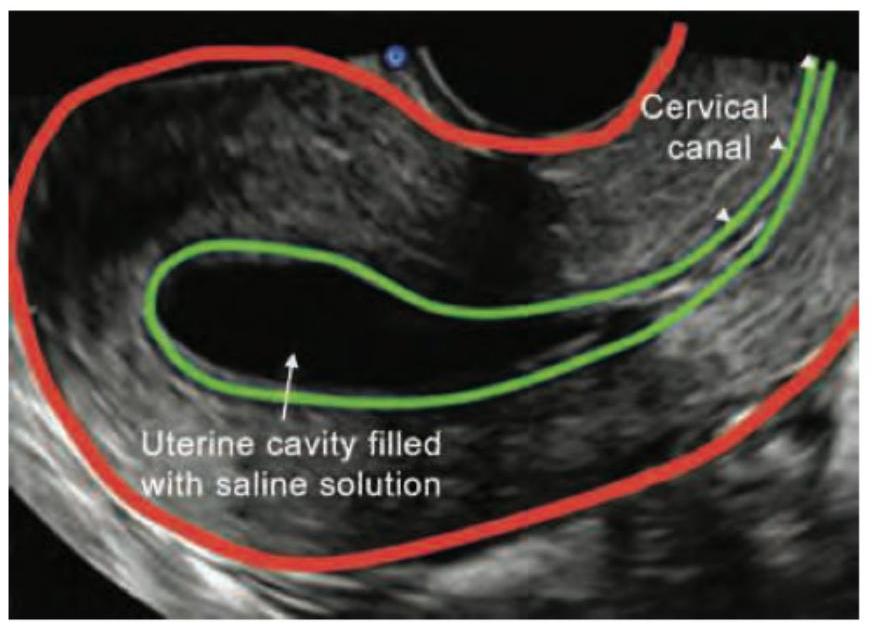

Identify the imaging procedure shown in the image.

Explanation: ***Saline infusion sonography*** - The image clearly shows the "uterine cavity filled with **saline solution**" seen on an **ultrasound** image, which is the hallmark of saline infusion sonography (SIS). - SIS, also known as **sonohysterography**, is used to evaluate the uterine cavity for abnormalities such as polyps, fibroids, or adhesions by distending the cavity with saline. *Hysterosalpingography* - This procedure uses **X-rays** and an **iodine-based contrast dye** to visualize the uterus and fallopian tubes, not ultrasound and saline. - While it also evaluates the uterine cavity, the imaging modality and contrast agent are different. *Pelvic ultrasound* - A standard pelvic ultrasound does not involve the **infusion of saline** into the uterine cavity. - While it can visualize the uterus, the detailed assessment of the **endometrial lining** and cavity shape is limited without uterine distension. *MRI of pelvis* - Magnetic resonance imaging (MRI) uses **magnetic fields** and radio waves to create detailed cross-sectional images of pelvic organs. - It does not involve the use of **saline infusion** into the uterine cavity for diagnostic purposes as shown in the image.